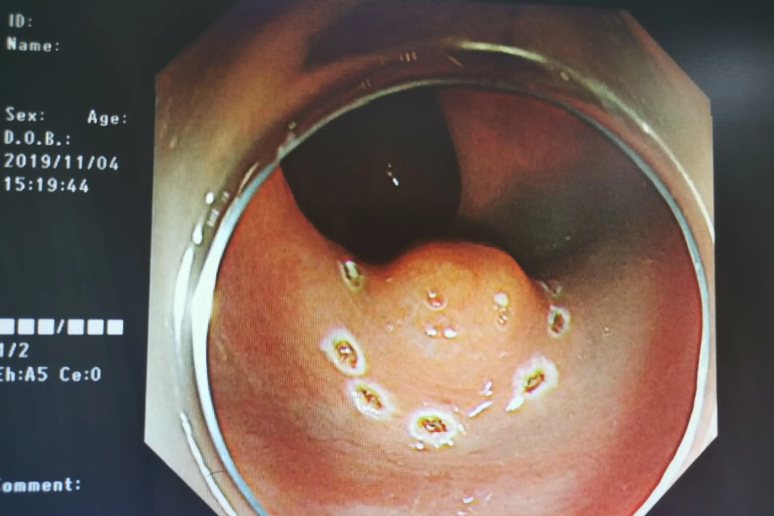

2.低位直肠肿瘤

低位直肠肿瘤表现为大便带血,一般呈鲜红色或者暗红色,位于大便表面之上,一般不与大便混合;大便次数增加;里急后重;大便性状改变,例如大便不成形或者便秘;肿瘤较大时,可能引起肠梗阻;晚期直肠癌患者还可以有贫血,消瘦等症状。